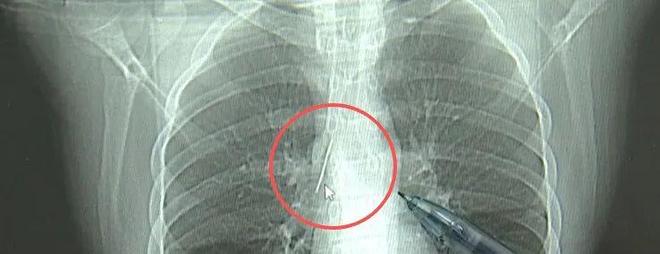

近日,安徽17岁小伙小陆参加征兵体检,胸片结果显示:胸腔内有一处金属高密度影,形态细长,像一根针。进一步的CT检查确认,异物是一枚金属针,斜插在肺组织内,位置十分凶险。

17岁小伙小陆参加征兵体检,发现胸腔内有根5cm缝衣针

家人赶紧带着小陆到西湖大学医学院附属杭州市第一人民医院就医。接诊的心胸外科副主任冯兴表示:“这根针的尖锐部,正好指向他体内的一个大血管,边上是上腔静脉和胸主动脉,这根针稍有不慎,就有可能造成周边血管的损伤,甚至危及生命。”